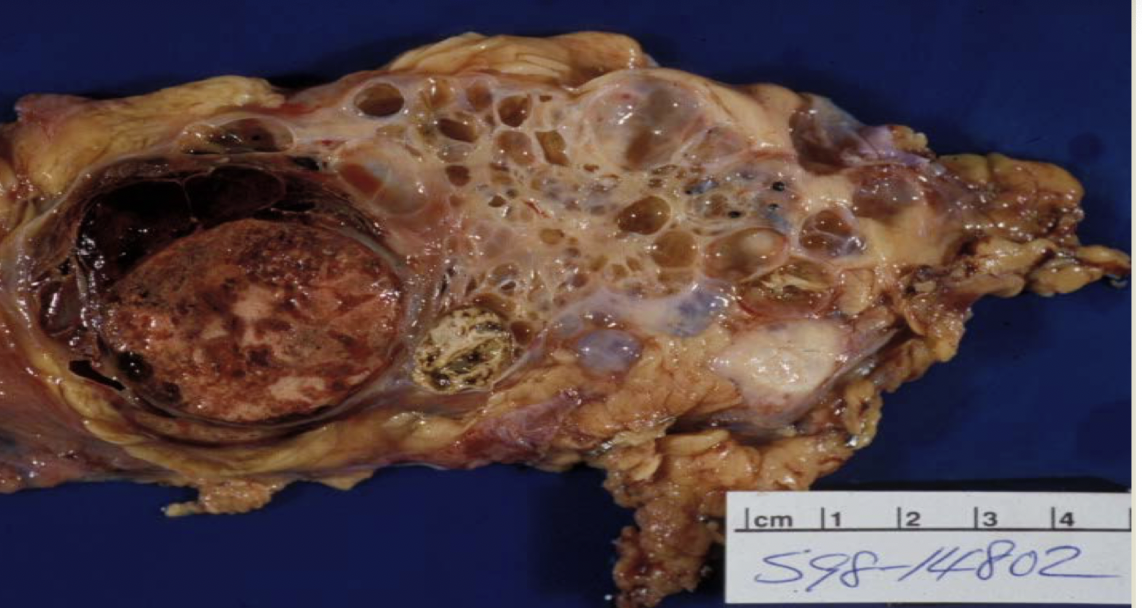

clear cell RCC

most common RCC

arise from proximal tubular epithelium

tendency to invade renal vein

von hippel-lindau syndrome (VHL)

buzzword: high HIF-1, increase VEGF and IGF-1

clear cell RCC

clear cell RCC

glycogen and lipid cytoplasm with rich vascular network

clear cell RCC

RCC type: -3p VHL

hematuria

most reliable cue for RCC

costovertebral

palpable mass

hematuria

clinical triad for RCC

lung, bone (LN, liver, adrenal glands, brain)

most common RCC mets to?